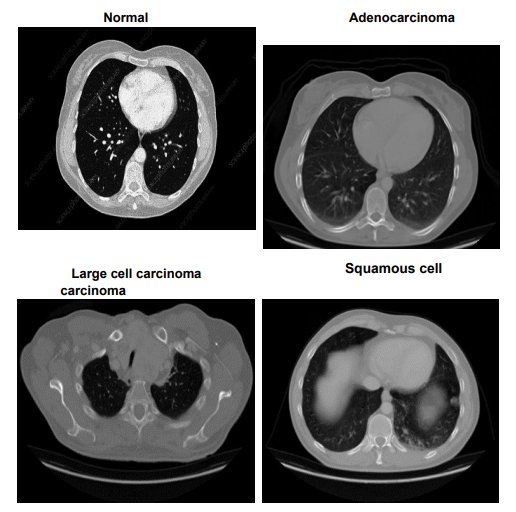

The Lung Cancer dataset provides a comprehensive examination of chest conditions through images stored in both JPEG and PNG formats, classifying them into Adenocarcinoma, Large cell carcinoma, Squamous cell carcinoma, and Normal. This dataset is organized into 'test', 'train', and 'valid' folders, partitioned to represent 20%, 70%, and 10% of the dataset, respectively. Figure 3 displays representative images from each category, illustrating the distinct characteristics of 'Adenocarcinoma', 'Large cell carcinoma', 'Squamous cell carcinoma', and 'Normal' lung conditions. These

images serve as key visual references, supporting model training to accurately classify each type. The 'test' set comprises 315 images with 54 Normal, 120 Adenocarcinoma, 51 Large cell carcinoma, and 90 Squamous cell carcinomas. The 'train' set includes 613 images featuring 148 Normal, 195 Adenocarcinoma, 115 Large cell carcinoma, and 155 Squamous cell carcinomas, while the 'validation' set contains 72 images with 13 Normal, 23 Adenocarcinoma, 21 Large cell carcinoma, and 15 Squamous cell carcinomas. Adenocarcinoma, the most prevalent form of lung cancer, constitutes approximately 30% of lung cancer cases and 40% of non-small cell lung cancer (NSCLC) cases, typically manifesting in the outer regions of the lungs. Large cell carcinoma, known for its rapid growth, accounts for 10-15% of NSCLC cases and can appear anywhere in the lung. Squamous cell carcinoma, making up about 30% of NSCLC, is primarily found in the central regions of the lung and is often linked to smoking. This dataset’s detailed categorization and high-quality imaging make it an invaluable resource for developing diagnostic models that distinguish between different types of lung cancer, enhancing our understanding and management of this complex disease.

Figure 3: Sample Images from Lung Cancer Dataset